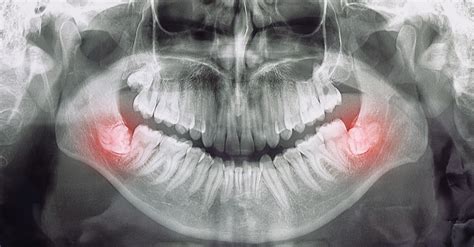

Dependiendo de cómo crezcan las muelas del juicio, pueden provocar distintos síntomas. Aunque las muelas del juicio crezcan con normalidad y erupcionen sin problemas, puede resultar desagradable. Las muelas del juicio suelen tardar en salir. Por eso puede ocurrir que el dolor remita y luego reaparezca. Lo mejor es concertar una cita con el dentista en cuanto notes que te están saliendo las muelas del juicio. Así el dentista podrá hacerte una radiografía de la mandíbula para determinar si tienes suficiente espacio en la boca o si es necesario extraer la muela del juicio antes de que erupcione.

- Muelas del juicio retenidas: Si las muelas del juicio no llegan a crecer en la boca, sino que permanecen en la mandíbula, se denominan "muelas del juicio retenidas". Las personas con muelas del juicio retenidas no suelen presentar síntomas. Sin embargo, si la muela del juicio se encuentra en un ángulo de la mandíbula y presiona un diente vecino, puede dañarlo. También pueden formarse quistes en las muelas del juicio retenidas, que el dentista puede reconocer en una radiografía. Los quistes están llenos de líquido y al principio no causan dolor.